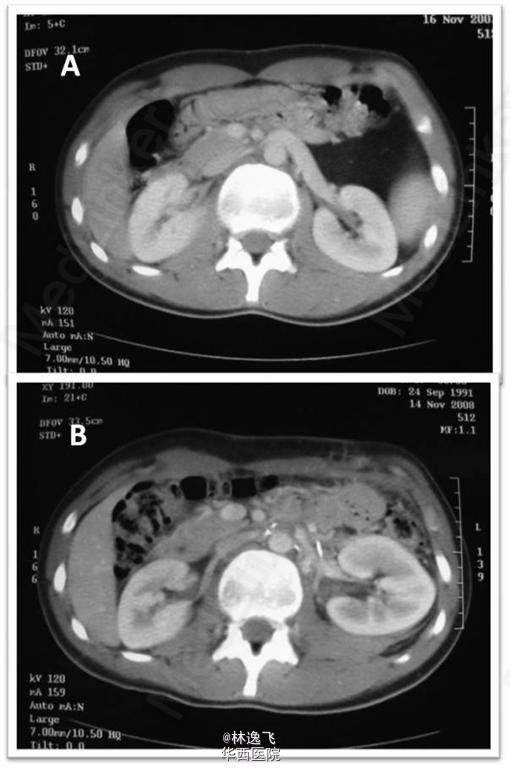

患者是17岁的男性青年患者,主诉左腰部钝痛数月,偶放射至左腹。无异常病史,麻醉可缓解疼痛。后疼痛频繁和加重,伴有肉眼血尿。不伴发热,且血流动力学稳定。仅有一次,由于诊断贫血,给与输注2U红悬。 辅助检查,患者有轻微的左侧精索静脉曲张。查血示低血红蛋白,尿常规示:蛋白尿。超声和尿路造影无特殊。腹部和骨盆的CT示,左肾静脉扩张。左肾可见一巨大脂肪瘤,加大的肾静脉的角度,使其穿过肠系膜上动脉的后面。(图1) 确诊后,手术切除脂肪瘤,缓解肠系膜上动脉对左肾静脉的压迫,将左肾静脉转位直接进入下腔静脉。 转自BJUI